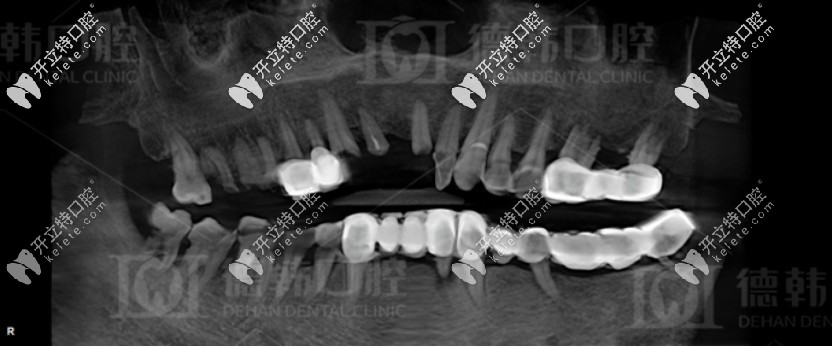

拔牙前爺爺?shù)恼掌?/strong>

沒有意識(shí)到牙齒缺失不修復(fù)的危害

德韓口腔先是對他進(jìn)行了全面的口腔檢查,發(fā)現(xiàn)其患有重度的牙周病,而且爺爺全口牙齒松動(dòng),牙列缺損,上下頜骨重度萎縮,無法保留口腔里的余牙,只能全部拔掉。

種植前爺爺?shù)难榔?/strong>